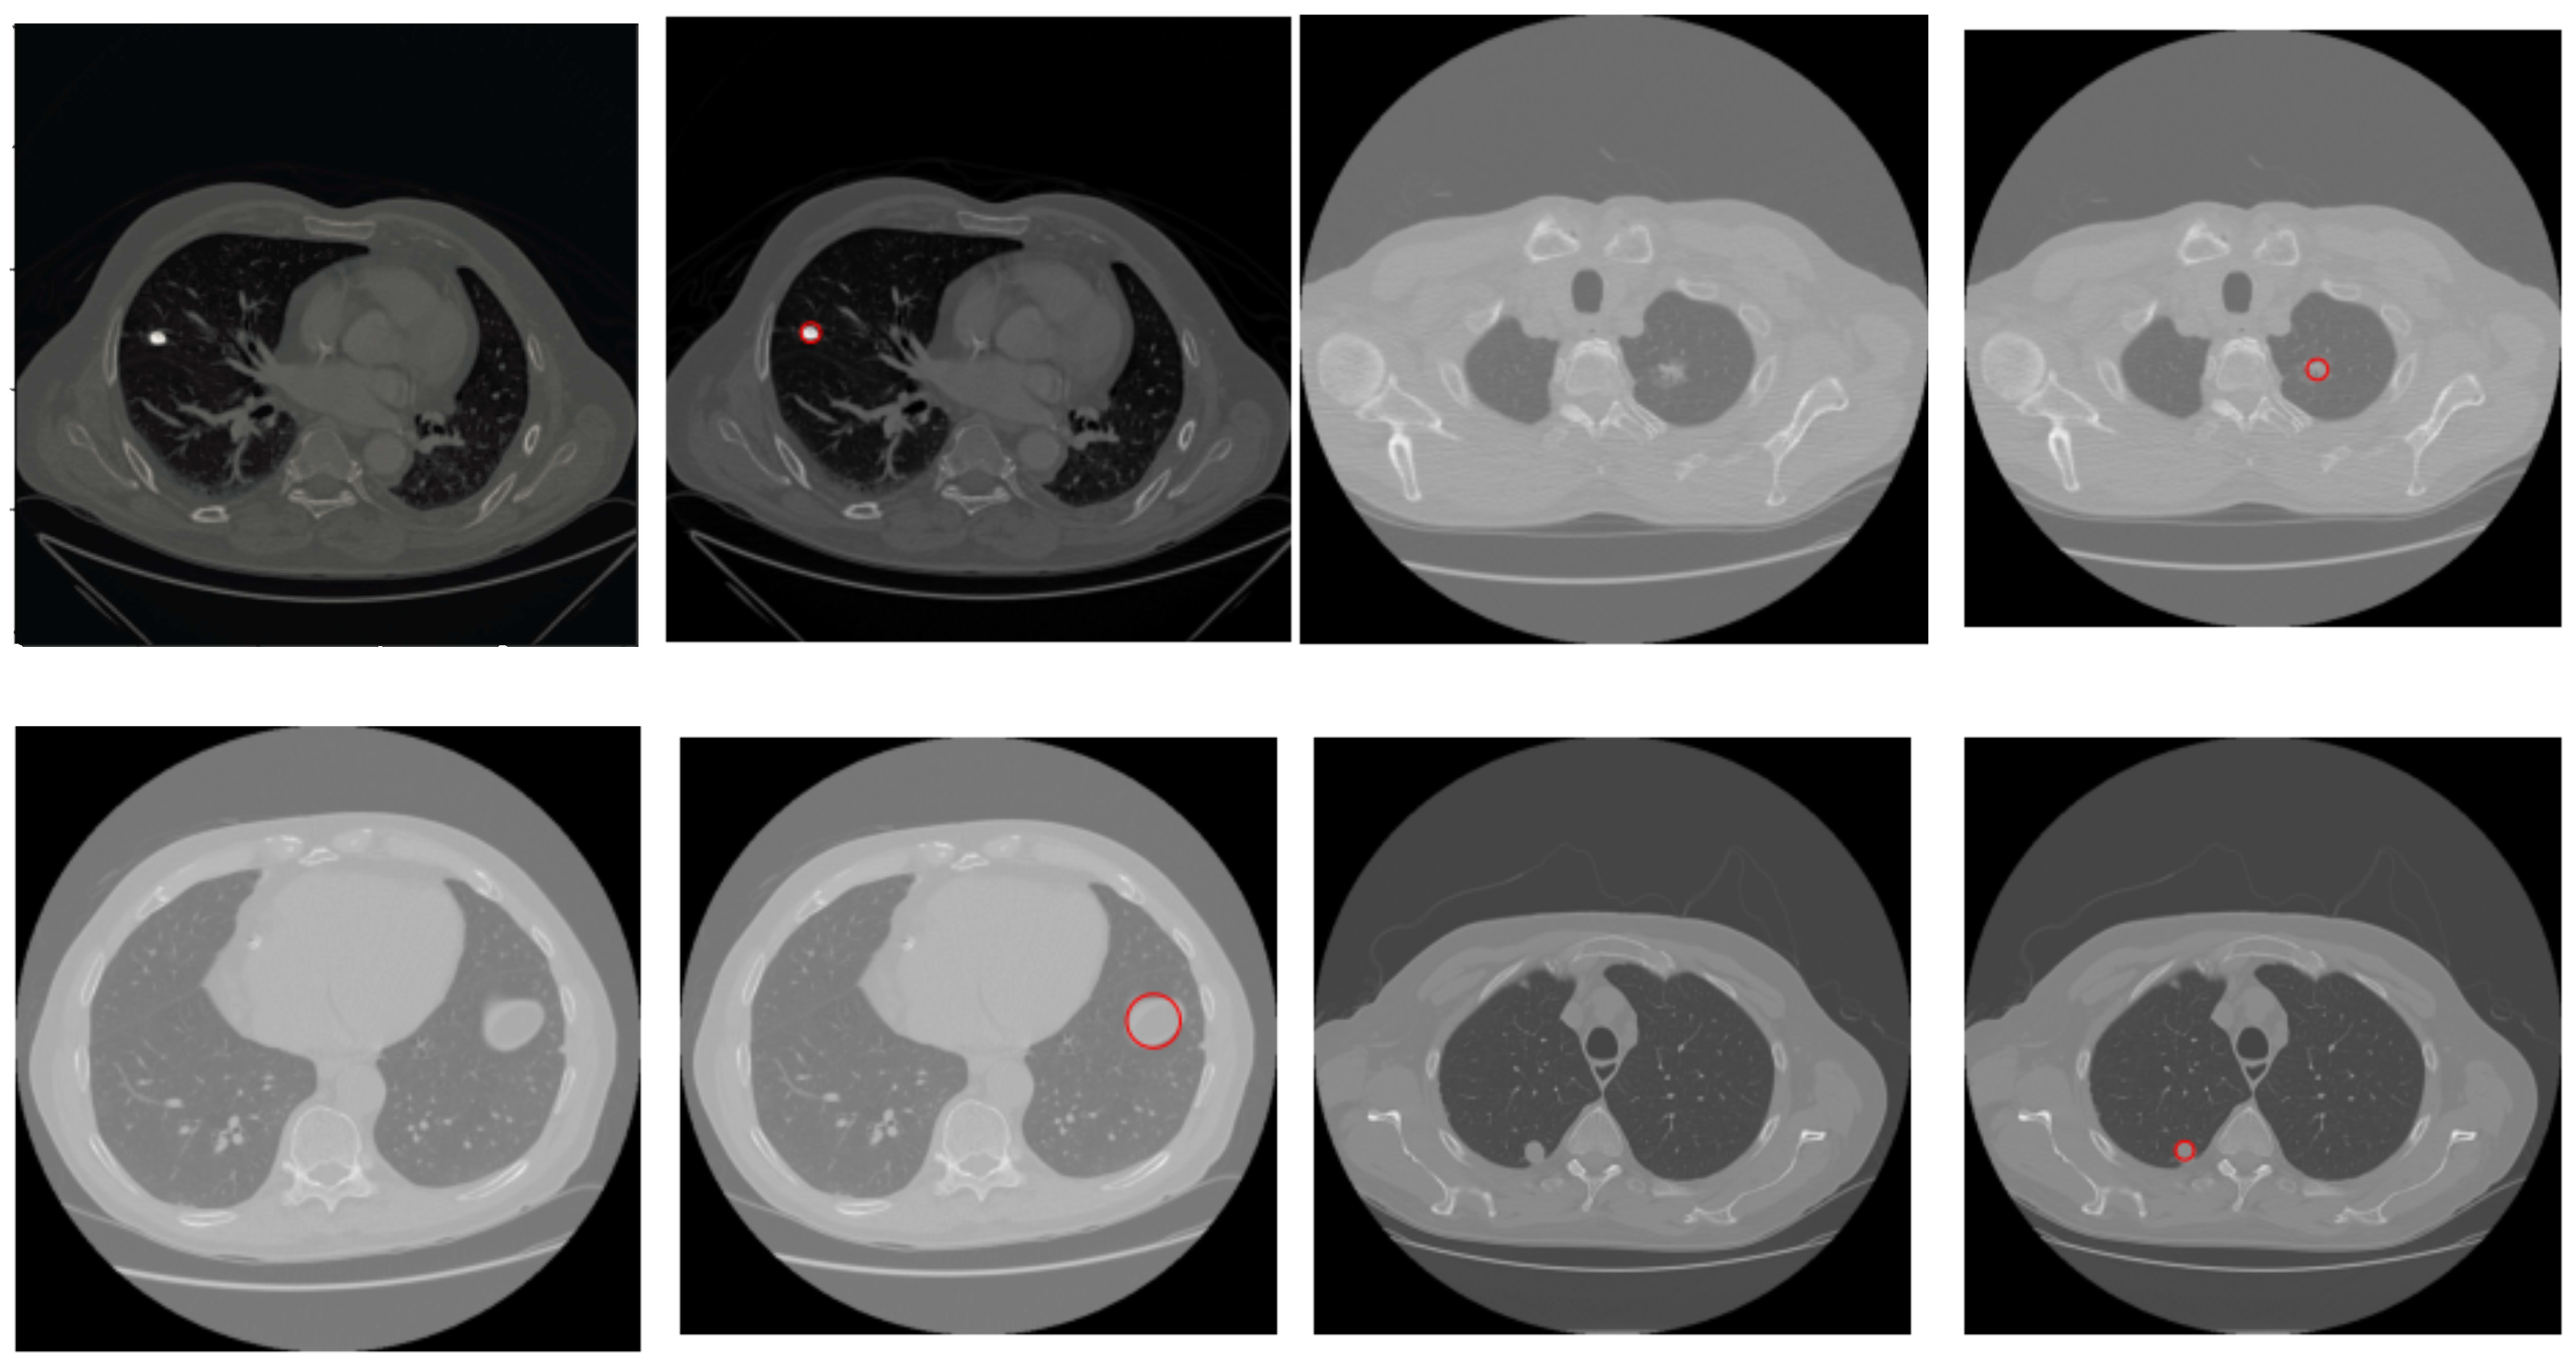

2.3. Nodule Detection

| Algorithm 1 Proposed Nodule Detection Algorithm |

| Require: A CT Image I of size Ensure: Detected nodule(s). 1: Normalize I to bring the intensity values within range 0–255 2: Suppress noise in I using Gaussian blur [] 3: if I is a lung window then 4: Compute histogram H of I 5:

Find the two local minima in H 6: [] ← multi-Otsu() 7: Threshold I using to separate lungs from rest of the lung window image 8: else {I is a mediastinal window} 9: {Compute the global mean of I} 10: Use to roughly separate divide I into two regions, and . 11: {Compute the local mean of the region } 12: {Compute the local mean of the region } 13: {The threshold is then taken as the average of the two local means} 14: Threshold I using to separate lungs from rest of the mediastinal window image 15: end if 16: Threshold I using threshold value This extracts vessels and nodules from the segmented lungs I. 17: I = OPEN (I) {OPEN is morphological binary open operator.} 18: I = CLOSE (I) {CLOSE is morphological binary open operator.} 19: Drop the objects in I that have the elongation feature, i.e., those that are not circular 20: Compute the diameter d of each lesion in I 21: if mm then 22: Mark the region as nodule 23: else mm 24: Mark the region as non-nodule 25: end if 26:Highlight the nodule regions, if any, using red circles |